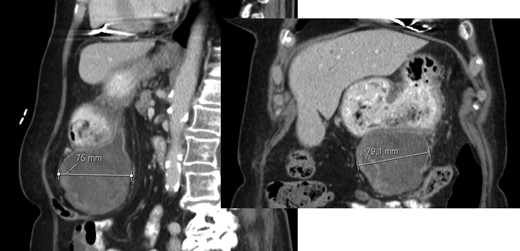

At 16 months, follow-up, local recurrence was identified on CT scan, showing an expansive heterogeneous lesion, below the stomach, with 7.4 cm of maximum diameter, showing no cleavage plan with the stomach (Fig. 4).

AP-CT – expansive heterogeneous lesion, with 7.4 cm, showing no cleavage plan with the stomach.